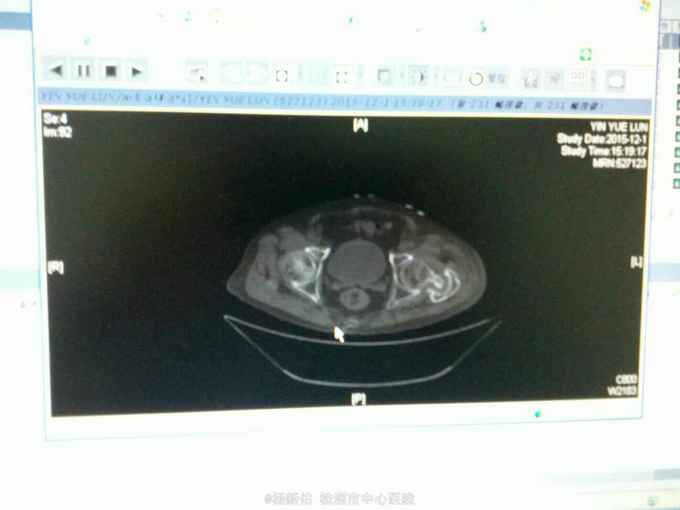

股骨粗隆间骨折并股骨干骨折

骨折 股骨粗隆间骨折 股骨干骨折

意外摔伤左下肢2天入院,2年前外伤至左股骨粗隆间骨折,未做治疗。尿毒症多年,目前透析3次/周

左大腿畸形,反常活动,左髋关节活动受限,

左股骨下段骨折,左股骨粗隆间骨折(阵旧性,骨不连),尿毒症。家属要求手术。